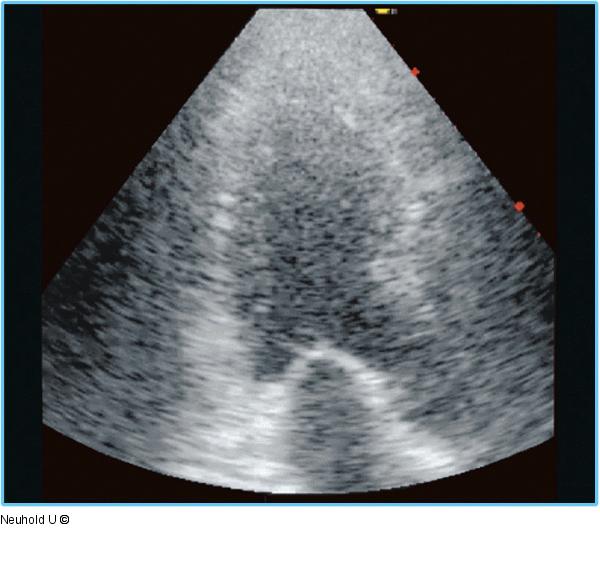

Abbildung 3: Dreikammerblick Dreikammerblick mit sichtbarem Papillarmuskelabriß, angedeutete Hypokinesie posterolateral. |

Dreikammerblick mit sichtbarem Papillarmuskelabriß, angedeutete Hypokinesie posterolateral. |